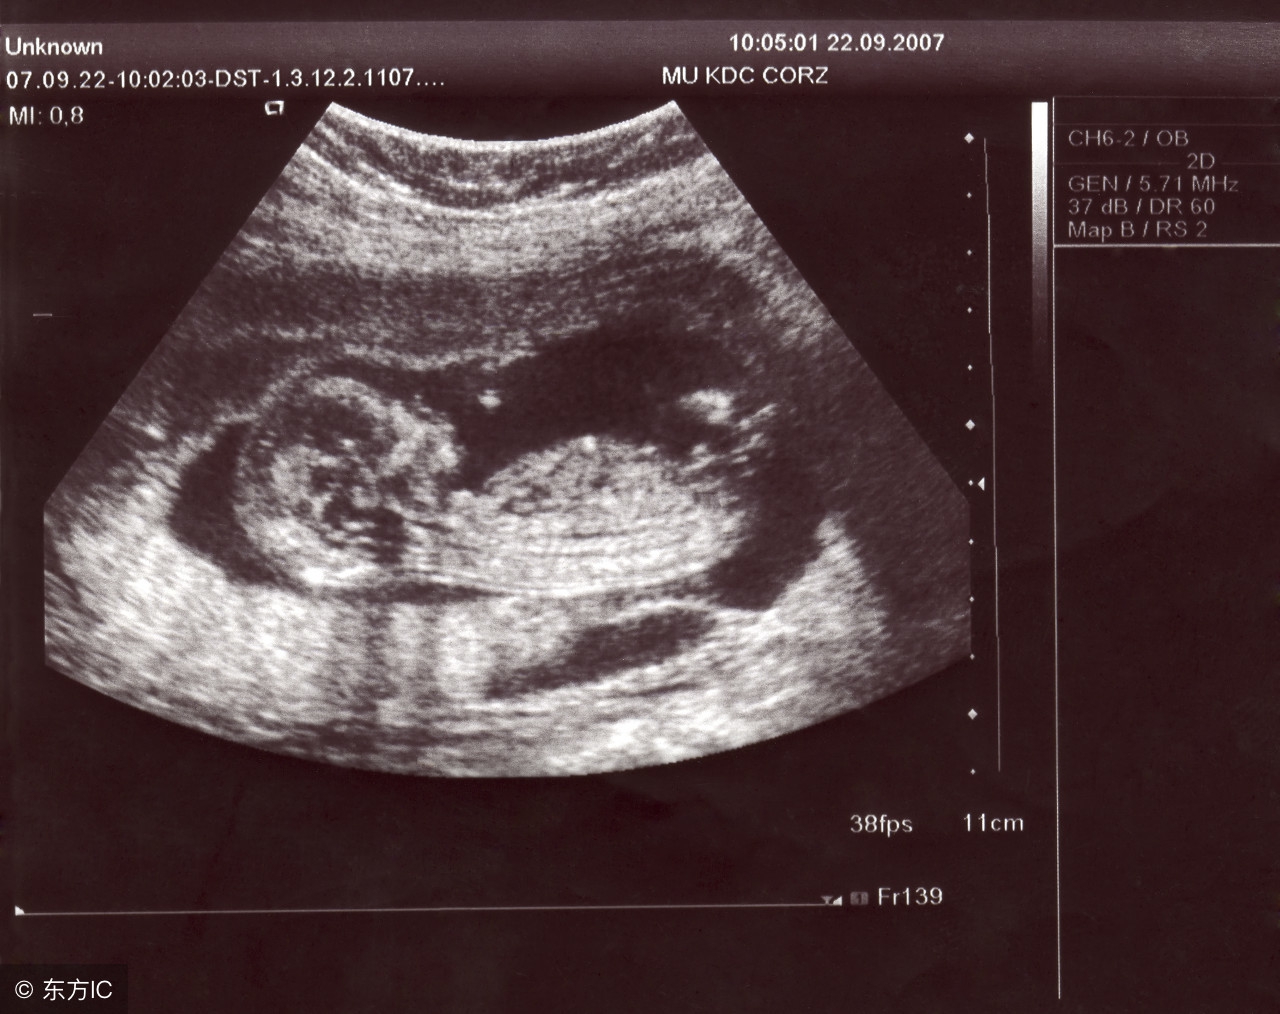

若是在怀孕6~7周时超声检查仍不见胎心出现,就要怀疑是否是“萎缩性胚囊”。因为,自然因素而导致流产的几率高达15%~20%。胚胎萎缩有60%左右是因为受精卵染色体异常,或受精卵本身有问题所致,因此,这并不是由准爸爸准妈妈的粗心大意造成,而是自然淘汰的结果。遇到此类情况,父母双方首先应做坦然接受,并配合医师做适当处理,才是应该有的正确态度。

发生产前出血时,应尽快就医并找出出血原因。超声波可得知有无前置胎盘,如确定无前置胎盘,则应进一步确诊是否有子宫颈或阴道疾病。另外,尿液检查及凝血功能测试也可提供进一步资讯。某些特殊情况,比如胎盘早期剥离,如果具备剖宫产的条件,以尽快生产为宜。